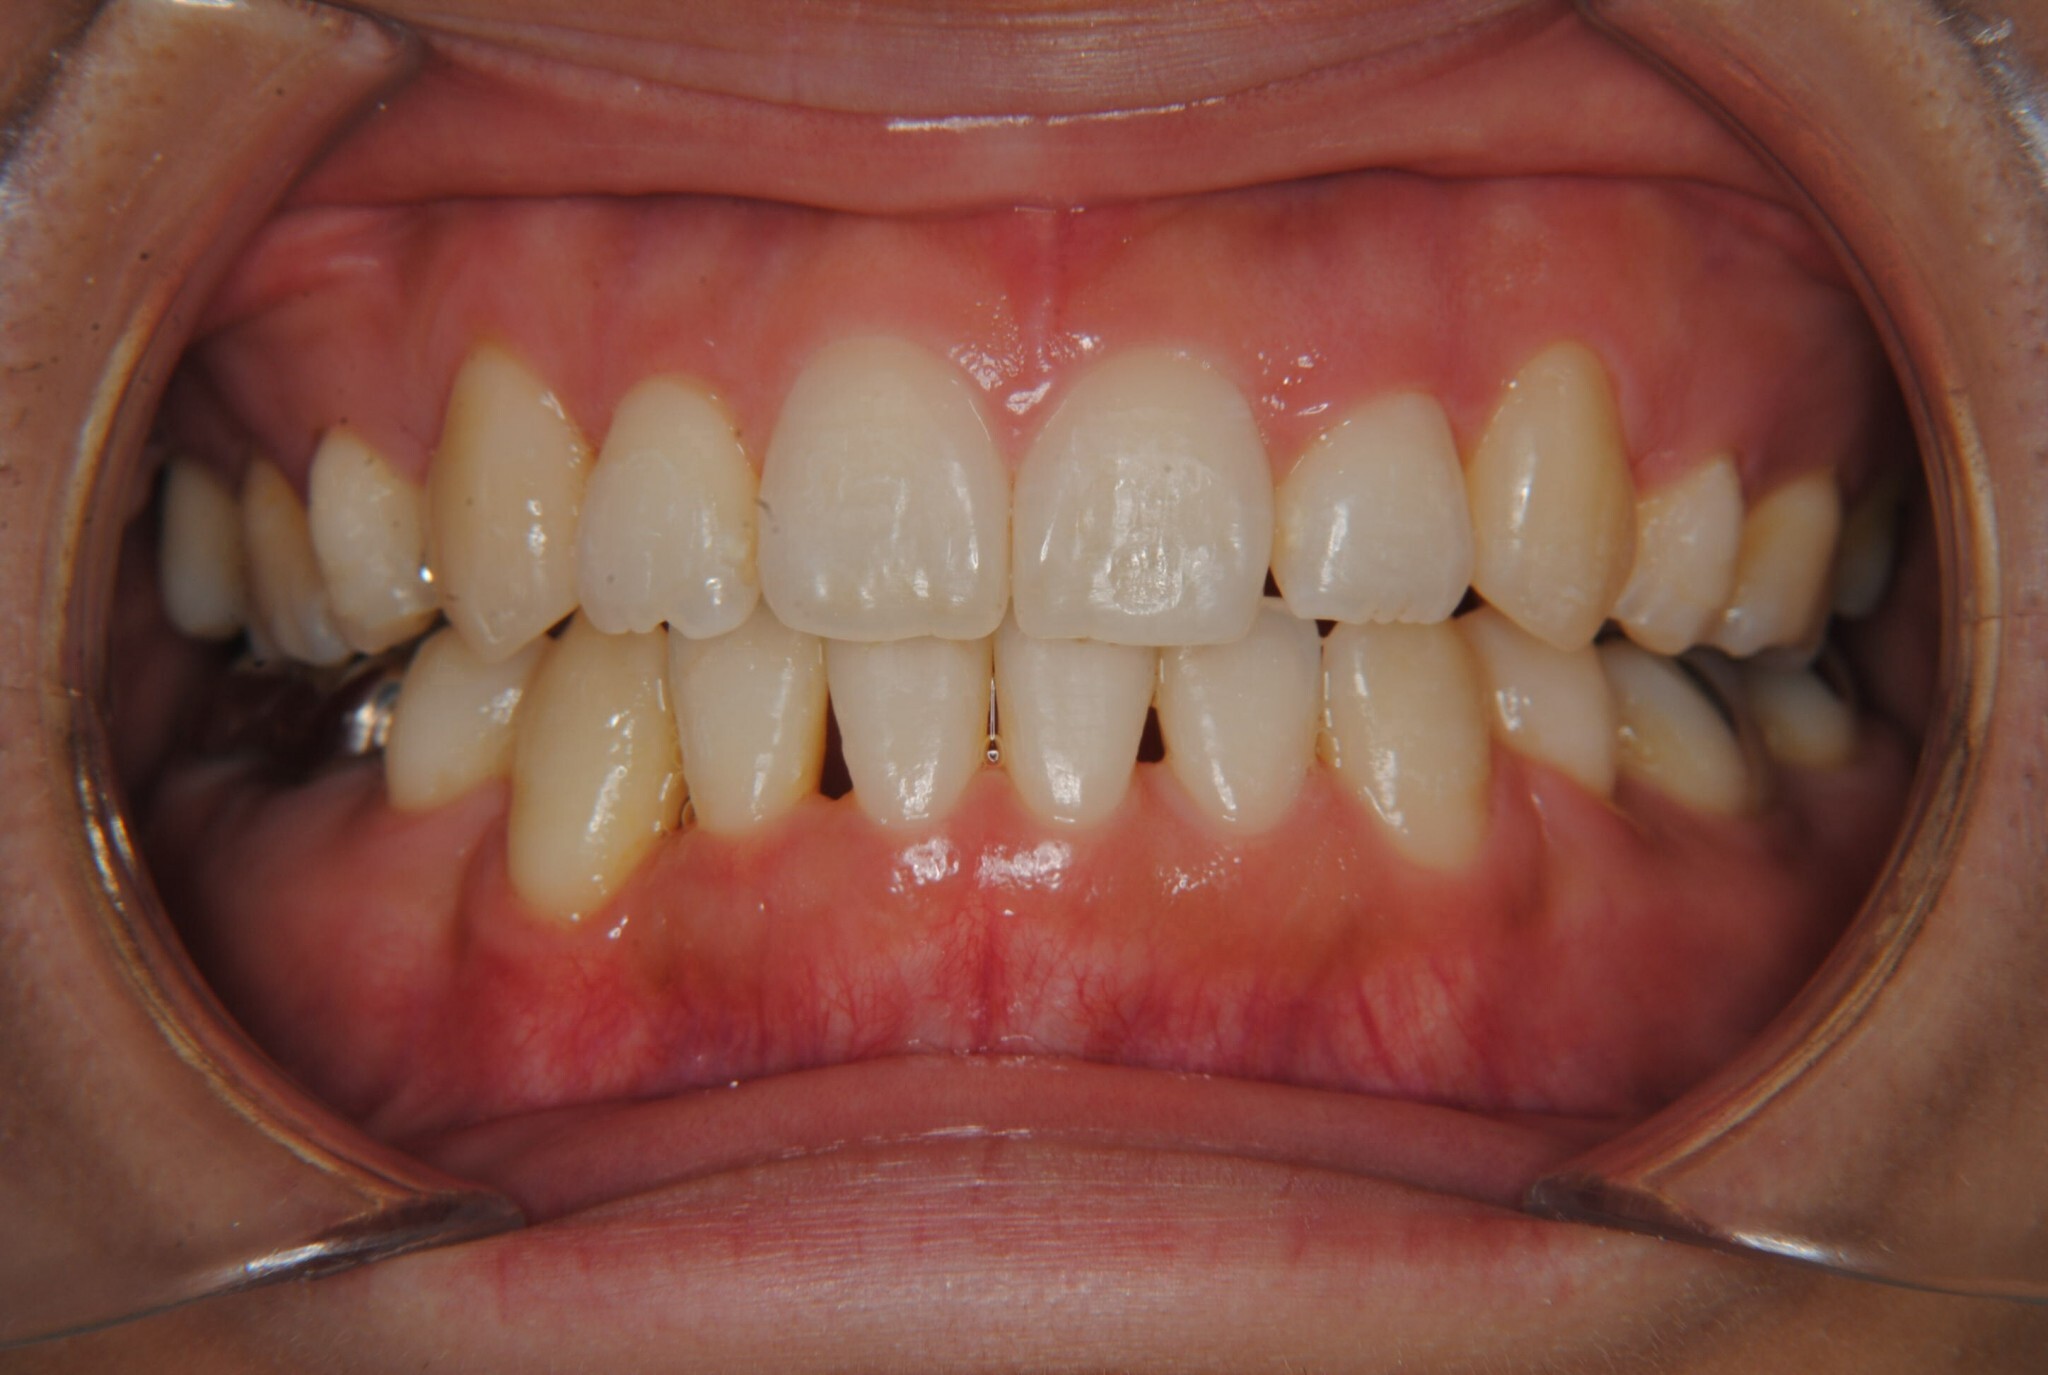

①主訴:八重歯、前歯のガタガタ、真ん中の不一致を治したい

②診断名:AngleⅠ級叢生

③年齢:治療開始時32歳10か月、動的治療終了時34歳5か月

④治療に用いた主な装置:マルチブラケット装置(T21ブラケット)

⑤抜歯部位:上下左右第一小臼歯

⑥治療期間:1年7ヶ月

⑧リスクと副作用:マルチブラケット装置(T21ブラケット)を初めてつけてから4日間、食事の時におもに前歯が少し痛かったとのことでした。治療後のエックス線写真で、歯根吸収はほとんど観察されず、歯肉を診ると残念ながら下顎前歯部に歯肉退縮(ブラックトライアングル)が生じていました。しかし、通常下顎前歯部は下唇に隠れてむき出しにはなっていないので、ご本人はあまり気にされていないご様子でホッとしています。